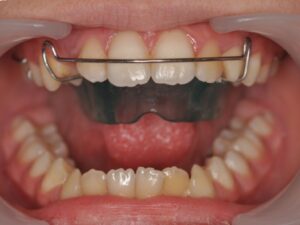

Il s’agit de l’orthodontie du jeune enfant. Elle permet d’intercepter un défaut de croissance ou d’éruption dentaire qui pourrait devenir irréversible s’il est pris en charge trop tard. De manière générale, il y a trois axes.

Il s’agit de la mastication, la respiration, la posture linguale, les habitudes déformantes. Elles font partie intégrante de la bonne posture des mâchoires et des dents. Elles seront également contrôlées et interceptées. Les appareils sont nombreux en fonction de la malocclusion, ils peuvent être fixes ou amovibles. Très souvent, l’interception pourra être associée à un rendez-vous chez : l'ORL, l'orthophoniste, le kinésithérapeute ou encore l'osthéopathe.